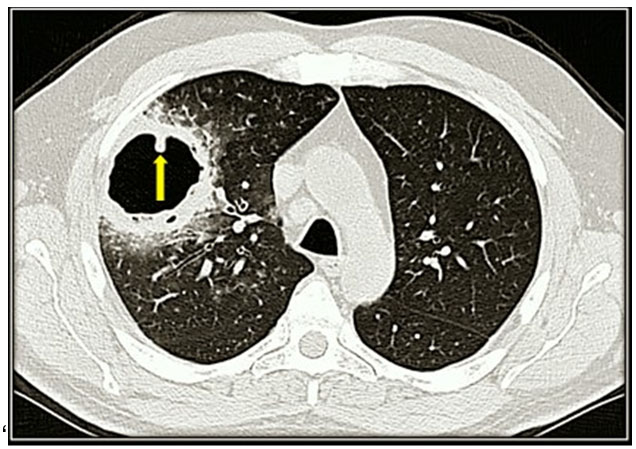

A 50-year-old man with a long history of heavy smoking presented to the Emergency Unit of the St. Anna Hospital, Ferrara, Italy, with cough and brown expectorate since about a month. The patient was afebrile. The physical examination did not disclose major findings apart from a marked reduction of vesicular murmur. Laboratory tests showed a normal white cell count, a significant increase of C-reactive protein (22.4 mg/dl; n.v.: (Figure 1) with features indicative of fungal hyphae (arrows in Figure 1). Urinary tests for pneumococcal and legionella antigens resulted negative as well as serology for Mycoplasma pneumoniae and Mycobacterium tuberculosis. Microbiological analysis on bronchoalveolar lavage fluid detected the presence of a Candida glabrata, whereas blood cultures were negative. Because of the resistance to antifungal treatments, a right superior lobectomy was needed and successfully performed. Six days after the operation the patient was discharged in good health with the recommendation of a respiratory rehabilitation for the next three months.

Figure 1: CT scan showing a huge (maximal diameter: 6.5 cm) mycetoma in the upper lobe of the right lung.

Mycetomas in asymptomatic and non-immunosuppressed subjects are rare clinical condition and represent a challenge for physicians. From a radiological perspective, mycetomas are often seen in the upper lobe, typically as a mobile mass with an air crescent. Differential diagnosis includes neoplasms and hematomas. Medial management of mycetomas includes antibiotic or antifungal treatments that should be always attempted. However, as shown by this case, the efficacy of antibiotic or antifungal drugs is limited and surgery may be needed [1],[2],[3].